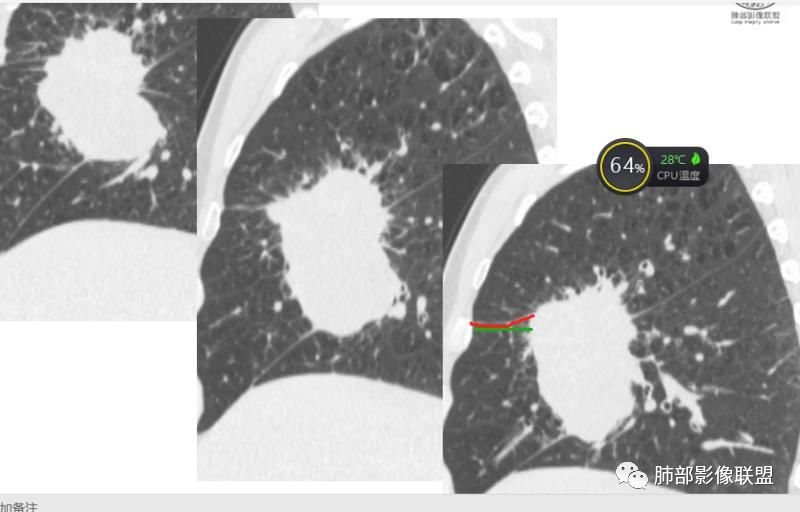

可以看到斜裂一侧往上一侧往下,那么就是说病灶应该是起源中叶,往上,往下侵犯这样

只有这个位置起源得才能做到,将叶间裂上下往不同方向推

斜裂向下推移了,水平裂向上推移了。

@吴婧南京市第一医院 这个从影像表现,坏死情况,以及叶裂推移情况与支气管推移情况来看,还是支持中叶间质来源,外朝内生长,同时向上,向下,向内都有推移作用。

下半段斜裂推移朝下

水平裂推移朝上

定在中叶应该没问题

上叶应该是侵犯,下叶应该是叶裂漏出来的。